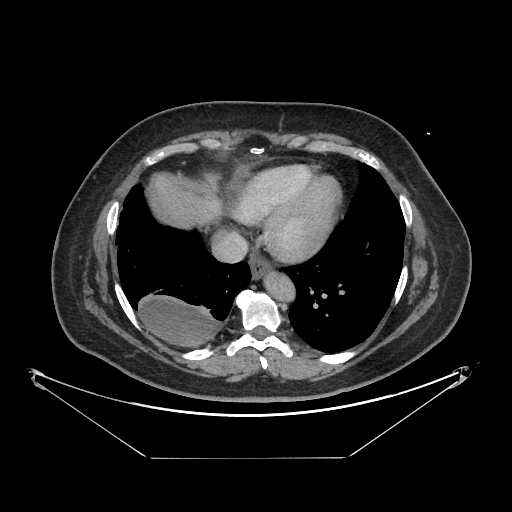

Image Grid

4Γ—3 grid: Rows show different image types (Original NATIVE, Reconstructed NATIVE, Original VENOUS, Generated VENOUS), Columns show windowing techniques (No Window, Lung Window, Mediastinum Window)

Original VENOUS CT scan

Full window (WL 1023.5, WW 4095 β†’ Low βˆ’1024, High +3071)

Mediastinum window (WL 40, WW 400 β†’ Low βˆ’160, High +240)